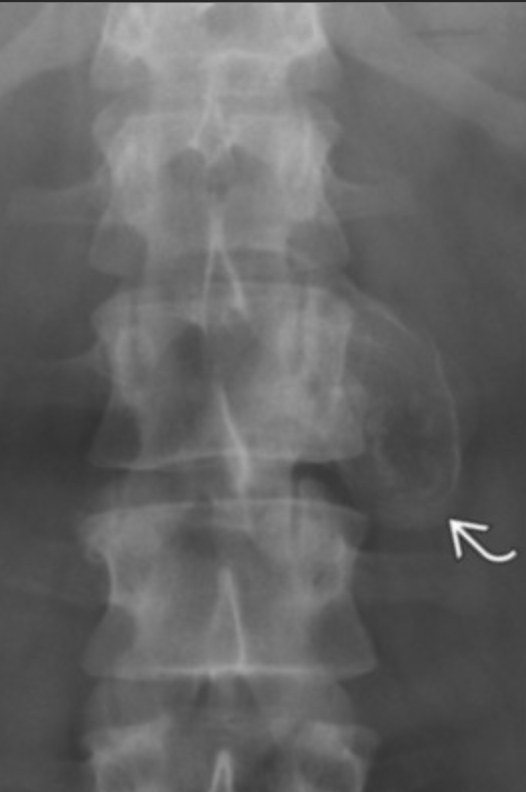

Pagets Disease

• Expansion of bone with thickened trabecula

• Multiple lesions

• Pelvis most commonly affected

• Almost never in fibula

• Blade of grass —> pointed appearance of lesion within the bone

• Secondary osteosarcoma can occur —> very bad